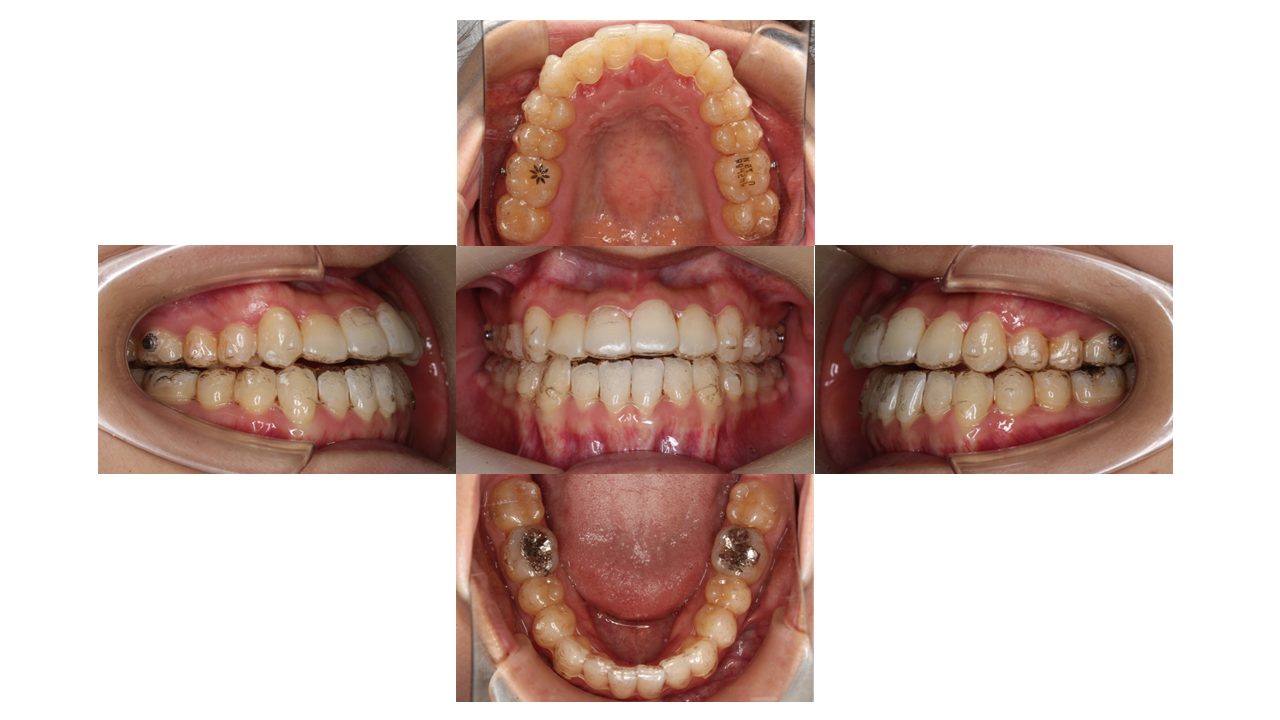

1年10か月経過の口腔内の状態です。

今回は、マウスピースを着用したまま口腔内写真を撮影しています。

全体的に凸凹が改善してきました。